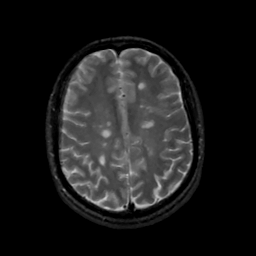

MR Study #14, June 2, 1991 -- Slice #35

[Home][Help][Clinical][Tour 1][Tour 2] Slice 35